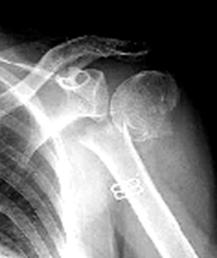

骨粗鬆症 骨量が減少し,骨の微細構造が破綻して、力学的強度が低下し骨折しやすくなった病態 (原発性骨粗鬆症の診断基準) |

大腿骨頚部骨折 脊椎圧迫骨折 手首の骨折 上腕骨骨折 |

【治療】@食事療法 乳製品が良い A適度な運動、日光浴 Bリハビリテーション→骨の萎縮を予防 C薬物治療 |